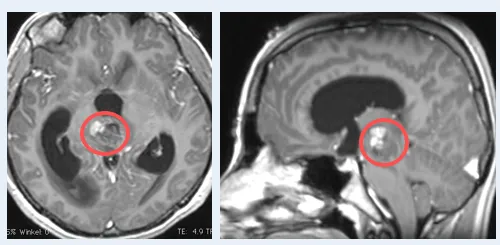

这台手术由巴特朗菲教授主刀。虽然病灶周围紧邻面听神经、三...